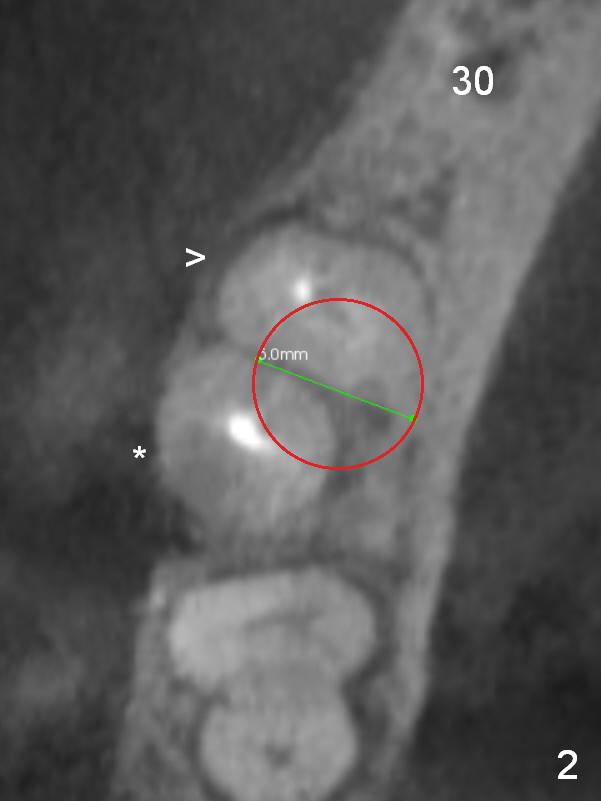

A 47-year-old woman has had 3 bridges. One of them (the lower right) is broken down. The patient requests removing the tooth #31 (Fig.1 CBCT), because of difficulty in keeping it clean. Since the buccal plate is thin (Fig.2 (axial section), 3 (coronal section) >) or absent (Fig.2 *), a 5 mm implant will be placed lingually (Clindamycin).